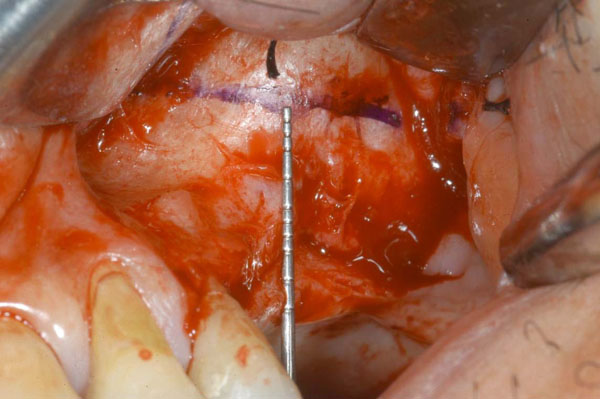

Fig. (3).

The AAA course is highlined on the lateral wall of the maxillary sinus using a surgical pencil.